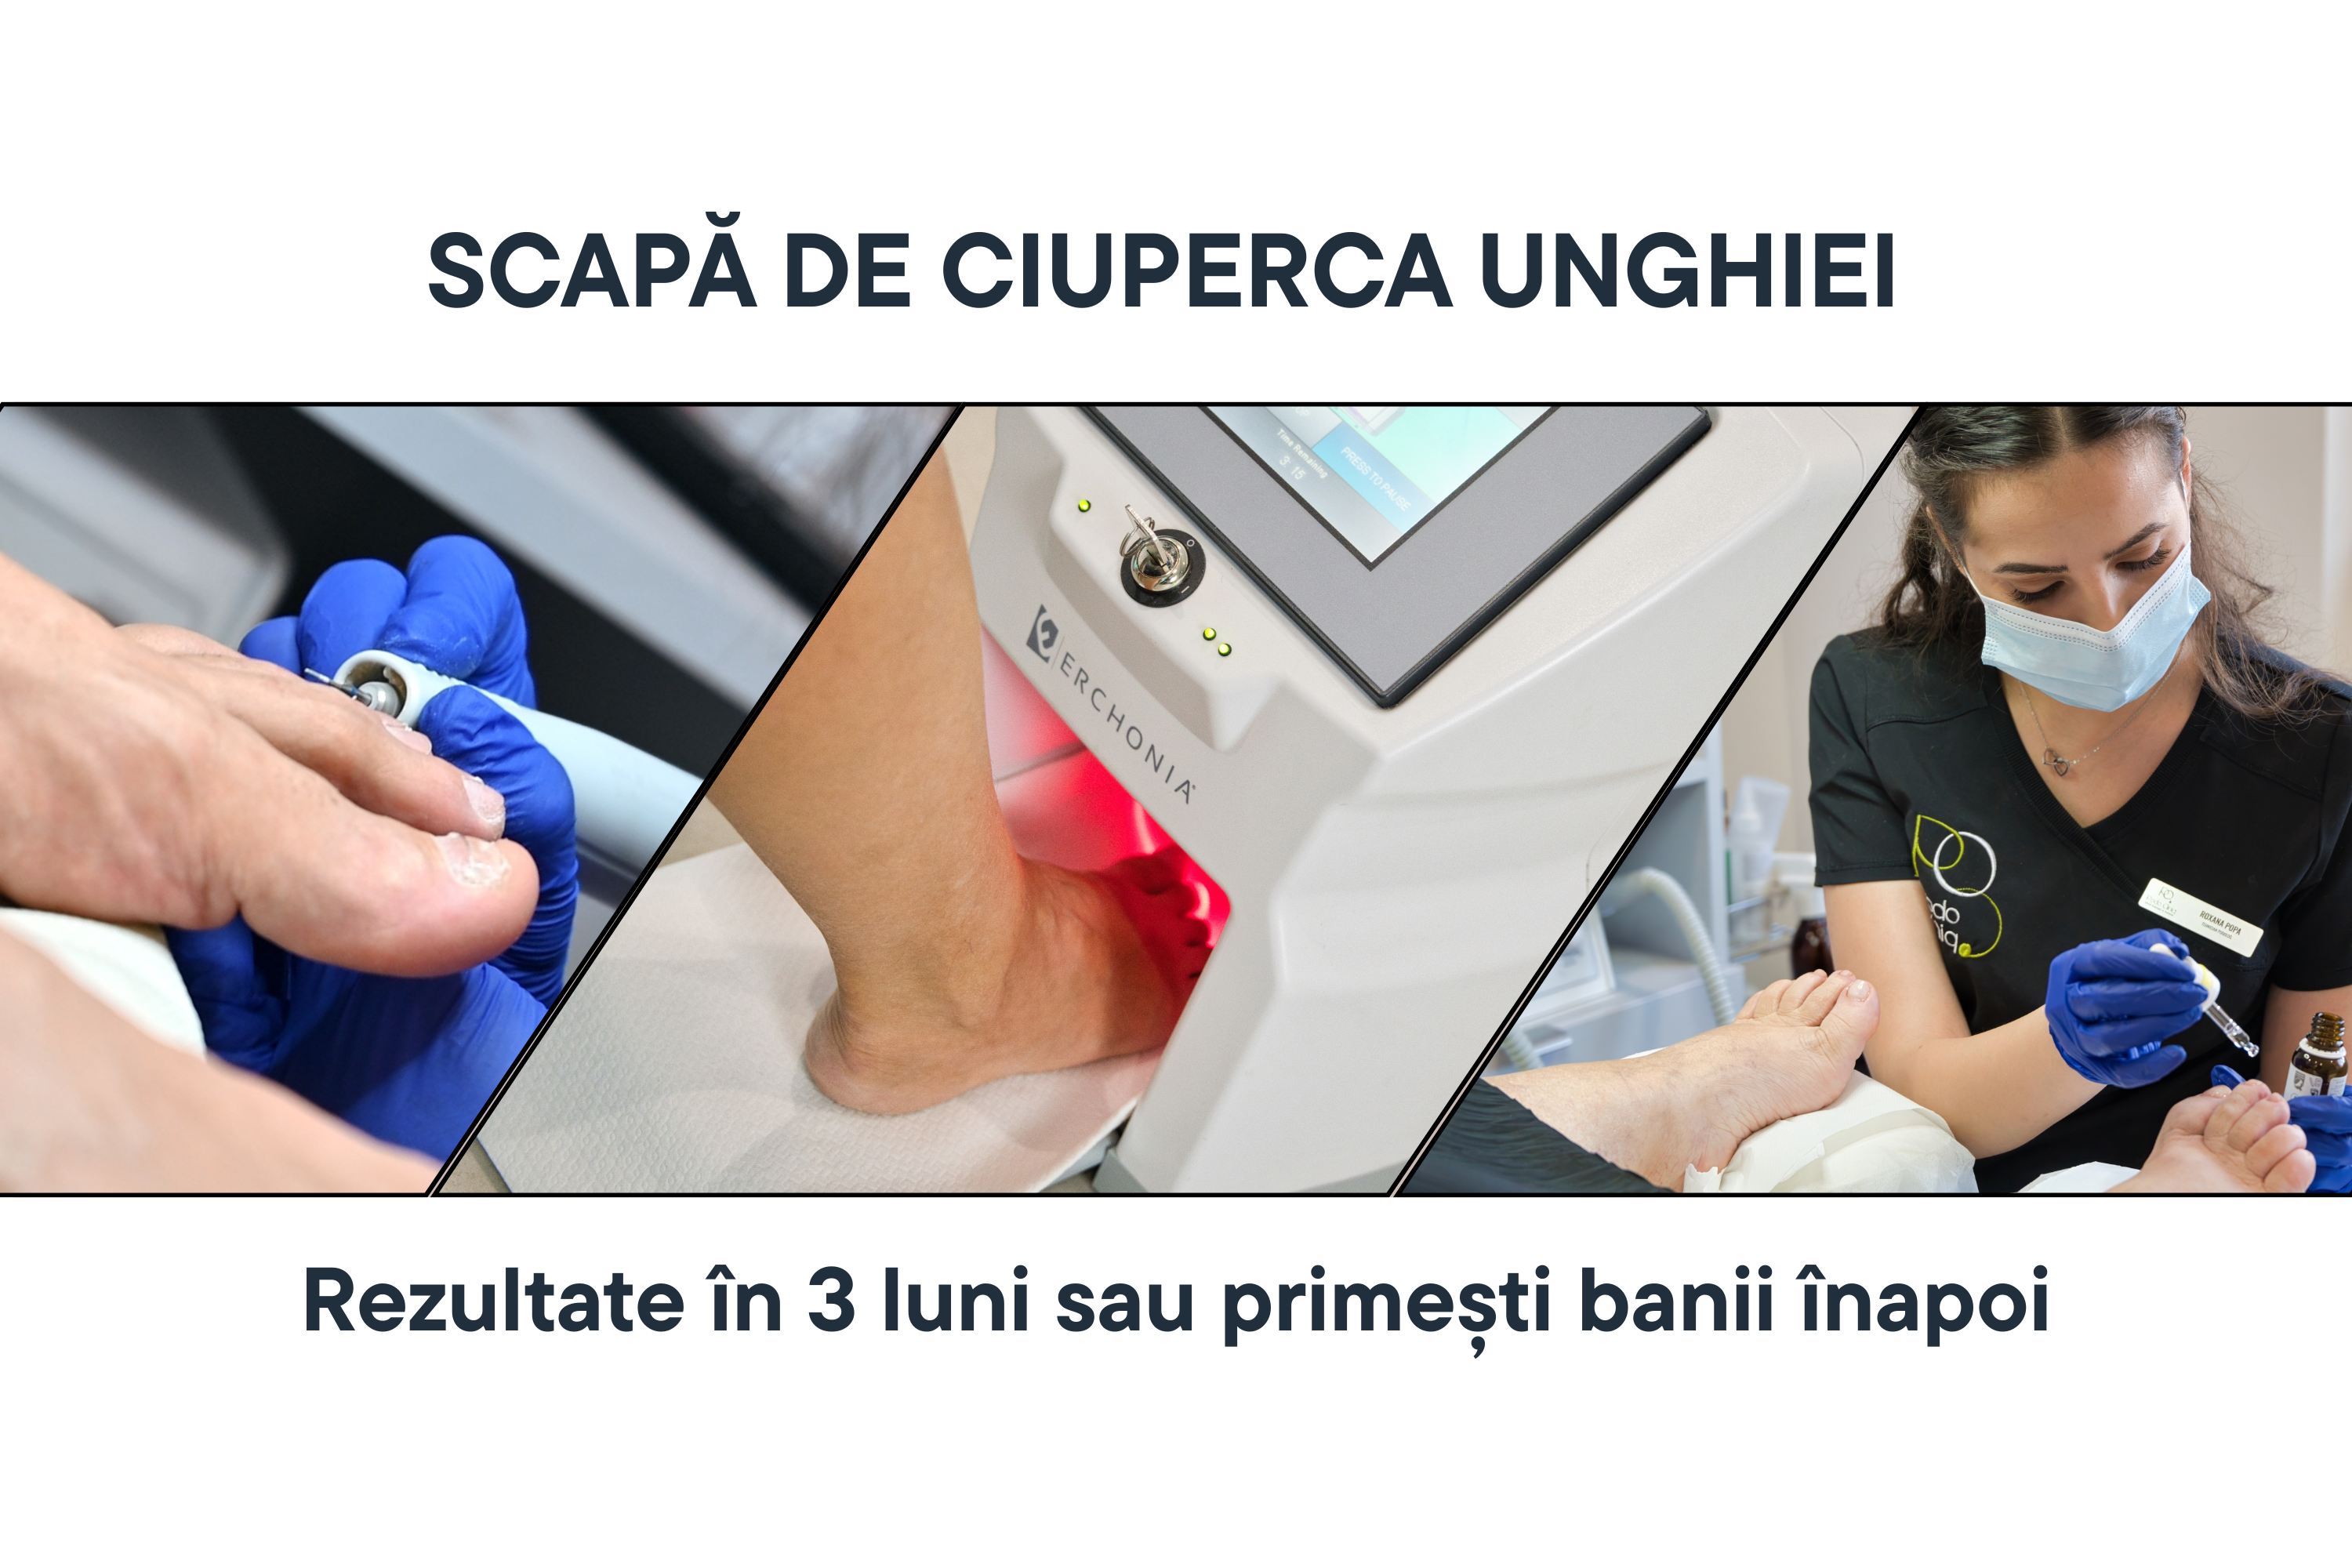

Tratament onicomicoza (ciuperca unghiei) cu laser Lunula, igienizări, terapii topice | PodoCliniq

Vreau Programare La PodoCliniq, folosim un protocol integrat care combină laserul Lunula (cu două lungimi de undă – una care acționează asupra fungilor și…